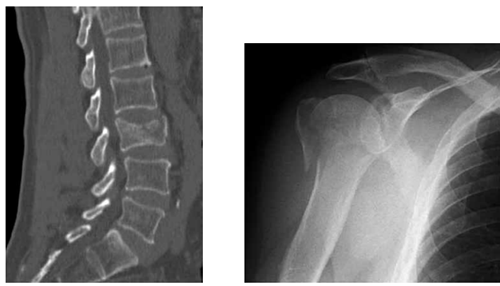

Uma paciente de 89 anos vem a consultório com histórico de queda após tropeçar no tapete de sua casa, há 10 meses, e ao escorregar no piso de seu banheiro, há 1 semana. Não tem antecedentes mórbidos. Relata somente que faz uso de alendronato 70 mg/semana, há 2 anos. Ela trouxe as radiografias realizadas por ocasião desses dois traumas. Seus exames laboratoriais estão normais.

Em função desse achado, foi realizada uma análise por meio da ferramenta Frax 2.0.

Diante do exposto, recomenda-se como tratamento para a paciente